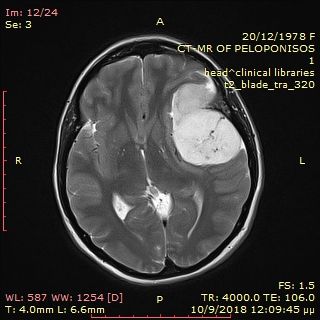

Preoperative cerebellar haemangioblastoma.

Postoperative cerebellar haemangioblastoma after total removal.